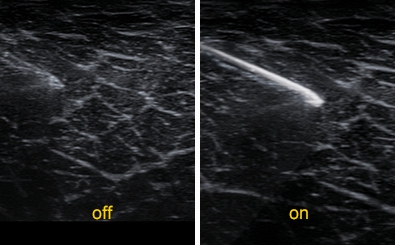

Needle VisionTM Plus